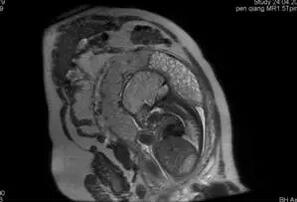

图:盆腔MRI提示部分性葡萄胎(伴一发育正常胎儿)